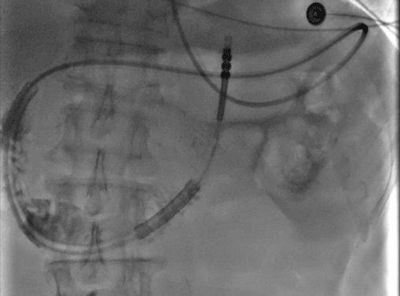

张荣副院长、张俊杰医生在DSA下置入肠梗阻导管

术后第一天,李老伯肠梗阻导管就引流出2400ml小肠液,从而使扩张的小肠迅速收缩,腹胀症状一下子就得到了缓解。

在肠道蠕动下,导管逐步深入,在到达1.8米后,无法继续下行,考虑到达梗阻点位置,在经过腹部平片确定好位置后,进行下一步手术松解治疗。